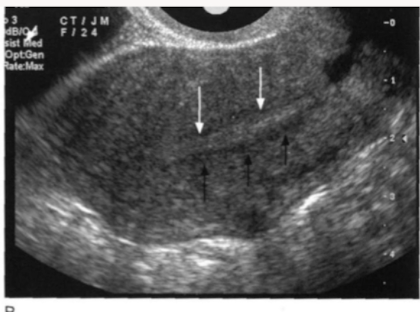

Identify the endometrial phase

early proliferative

Late proliferative (2 line sign)